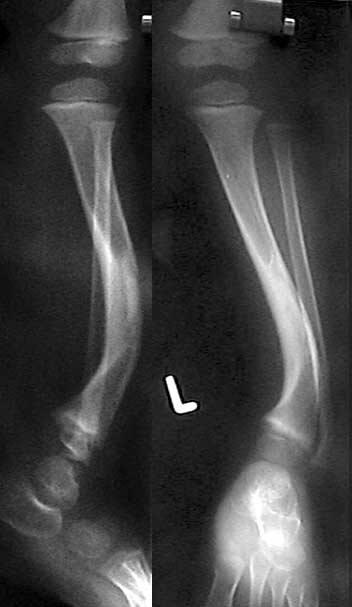

На консультативный прием родители привели ребенка 3 лет с деформацией левой голени.

Деформация была выявлена сразу после рождения ребенка и с его развитием усиливается хромота. При ходьбе ребенок полностью наступает на ногу, распределяя нагрузку на внешний край стопы. Нагрузка на ногу безболезненна, данных за травму или инфекцию нет. При осмотре кожных покровов отмечаются характерные пигментные пятна cafe au lait. Совокупность данных анамнеза и осмотра наводит на мысль о нейрофиброматозе с врожденным псевдоартрозом б\б кости. Рентгенограммы прилагаю. Заранее признателен за высказанные мнения по тактике лечения ребенка. С наилучшими пожеланиями, Евгений Чекашкин